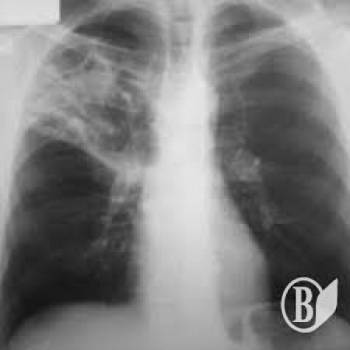

Хворих на туберкульоз залишили без ліків

ЧИТАЙТЕ ТАКОЖ: Вразливі категорії населення перевірили на туберкульоз